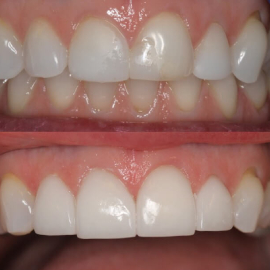

Ceramics can make a smile look nice again

Changes in bite position with comprehensive treatment

Opening the bite position provides a more stable

position also protecting the front teeth

Original bite position

Opened bite with upper restorations